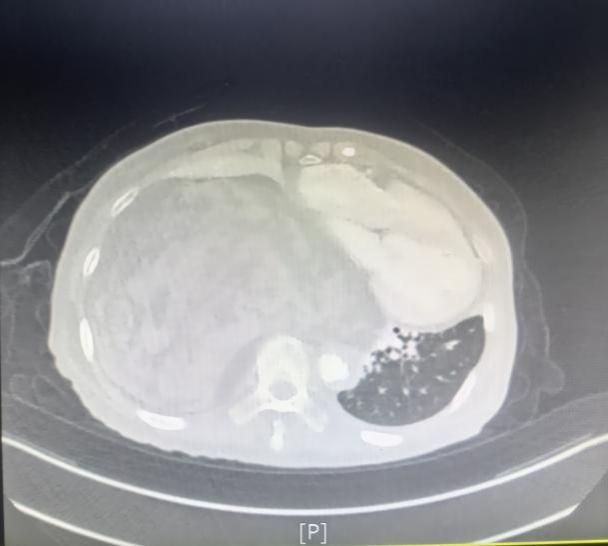

一年前,叶奶奶在体检中偶然发现纵隔占位性病变,当时肿瘤直径约 4 厘米,因无明显不适症状,且考虑到年龄较大,家属选择了保守观察。然而近半年来,患者逐渐出现活动后气喘、心慌等症状,近期更是发展到体力无法支撑正常行走,体重也随之下降。复查胸部 CT 显示,肿瘤已增至超过15厘米,占据右侧胸腔超过2/3空间,严重压迫心脏、大血管及食管,且与周围组织粘连致密,若不及时干预,随时可能因呼吸循环衰竭危及生命。

术中精细操作 + 术后科学康复 多学科全程护航